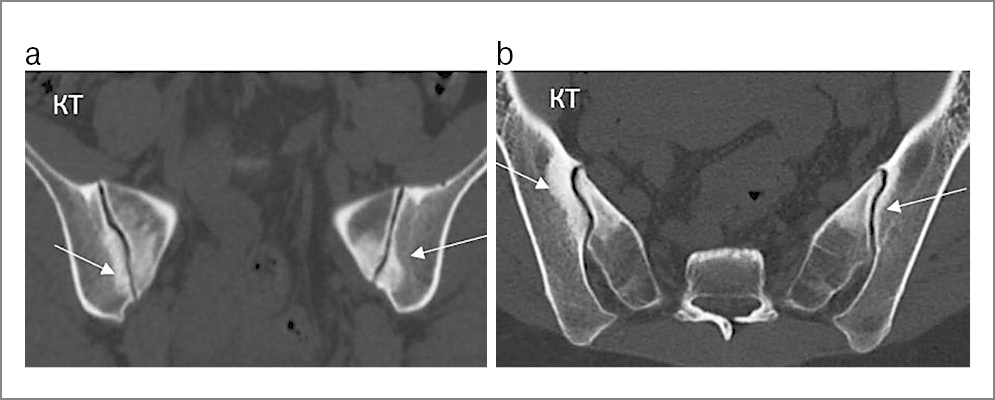

Конденсирующий остеит подвздошной кости и/или крестца. На рентгенограмме конденсирующий остеит выглядит как широкая зона склероза треугольной формы с основанием, направленным вниз. Эти изменения могут обнаруживаться в одной или обеих подвздошных костях и/или в крестце поблизости от КПС (рис. 15) и наблюдаются преимущественно у женщин (особенно после родов), но иногда и у мужчин (имеется связь с ожирением, чрезмерной физической нагрузкой и сколиозом позвоночника). Ширина суставной щели не изменяется и эрозии отсутствуют.

Рис. 15. Пациентка К. 32 лет. Жалобы на боли в нижней части спины в течение 5 лет, возникли после родов: на КТ крестцово-подвздошных сочленений в коронарной (a) и аксиальной (b) плоскостях в субхондральных отделах тел обеих подвздошных костей и боковых масса крестца наблюдаются зоны широкого склероза (указаны стрелками), ширина суставных щелей не изменена, замыкательные пластинки костей четкие, без узурации – двусторонний конденсирующий остеит подвздошных костей и крестца.

Клинические проявления непостоянны (чаще отсутствуют), но возможны боли в пояснице или в области КПС, причем воспалительного характера. На МРТ конденсирующий остеит характеризуется низкой интенсивностью сигнала во всех последовательностях (рис. 16). Часто (в 48–93% случаев) по периферии зоны склероза отмечается отек костного мозга. Почти всегда зоны отека у пациентов с конденсирующим остеитом расположены в передней части КПС (тогда как при аксСпА они располагаются преимущественно в средней части сустава), эрозии наблюдаются только в единичных случаях [22].